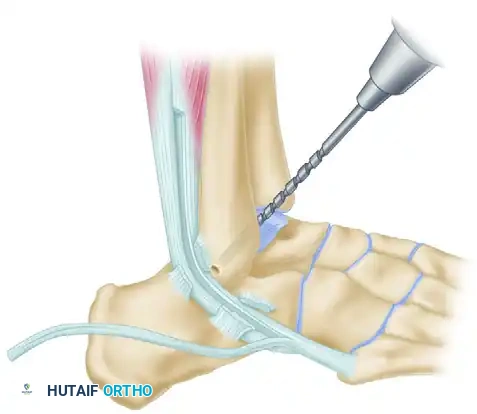

Step 4: Fibular Tunnel Preparation

Attention is turned to the lateral malleolus. Drill a 4.5-mm hole into the fibula from anterior to posterior, located approximately 1 cm proximal to the distal tip of the fibula.

Clear the tunnel of any bony debris using a curette to ensure smooth passage of the tendon graft.